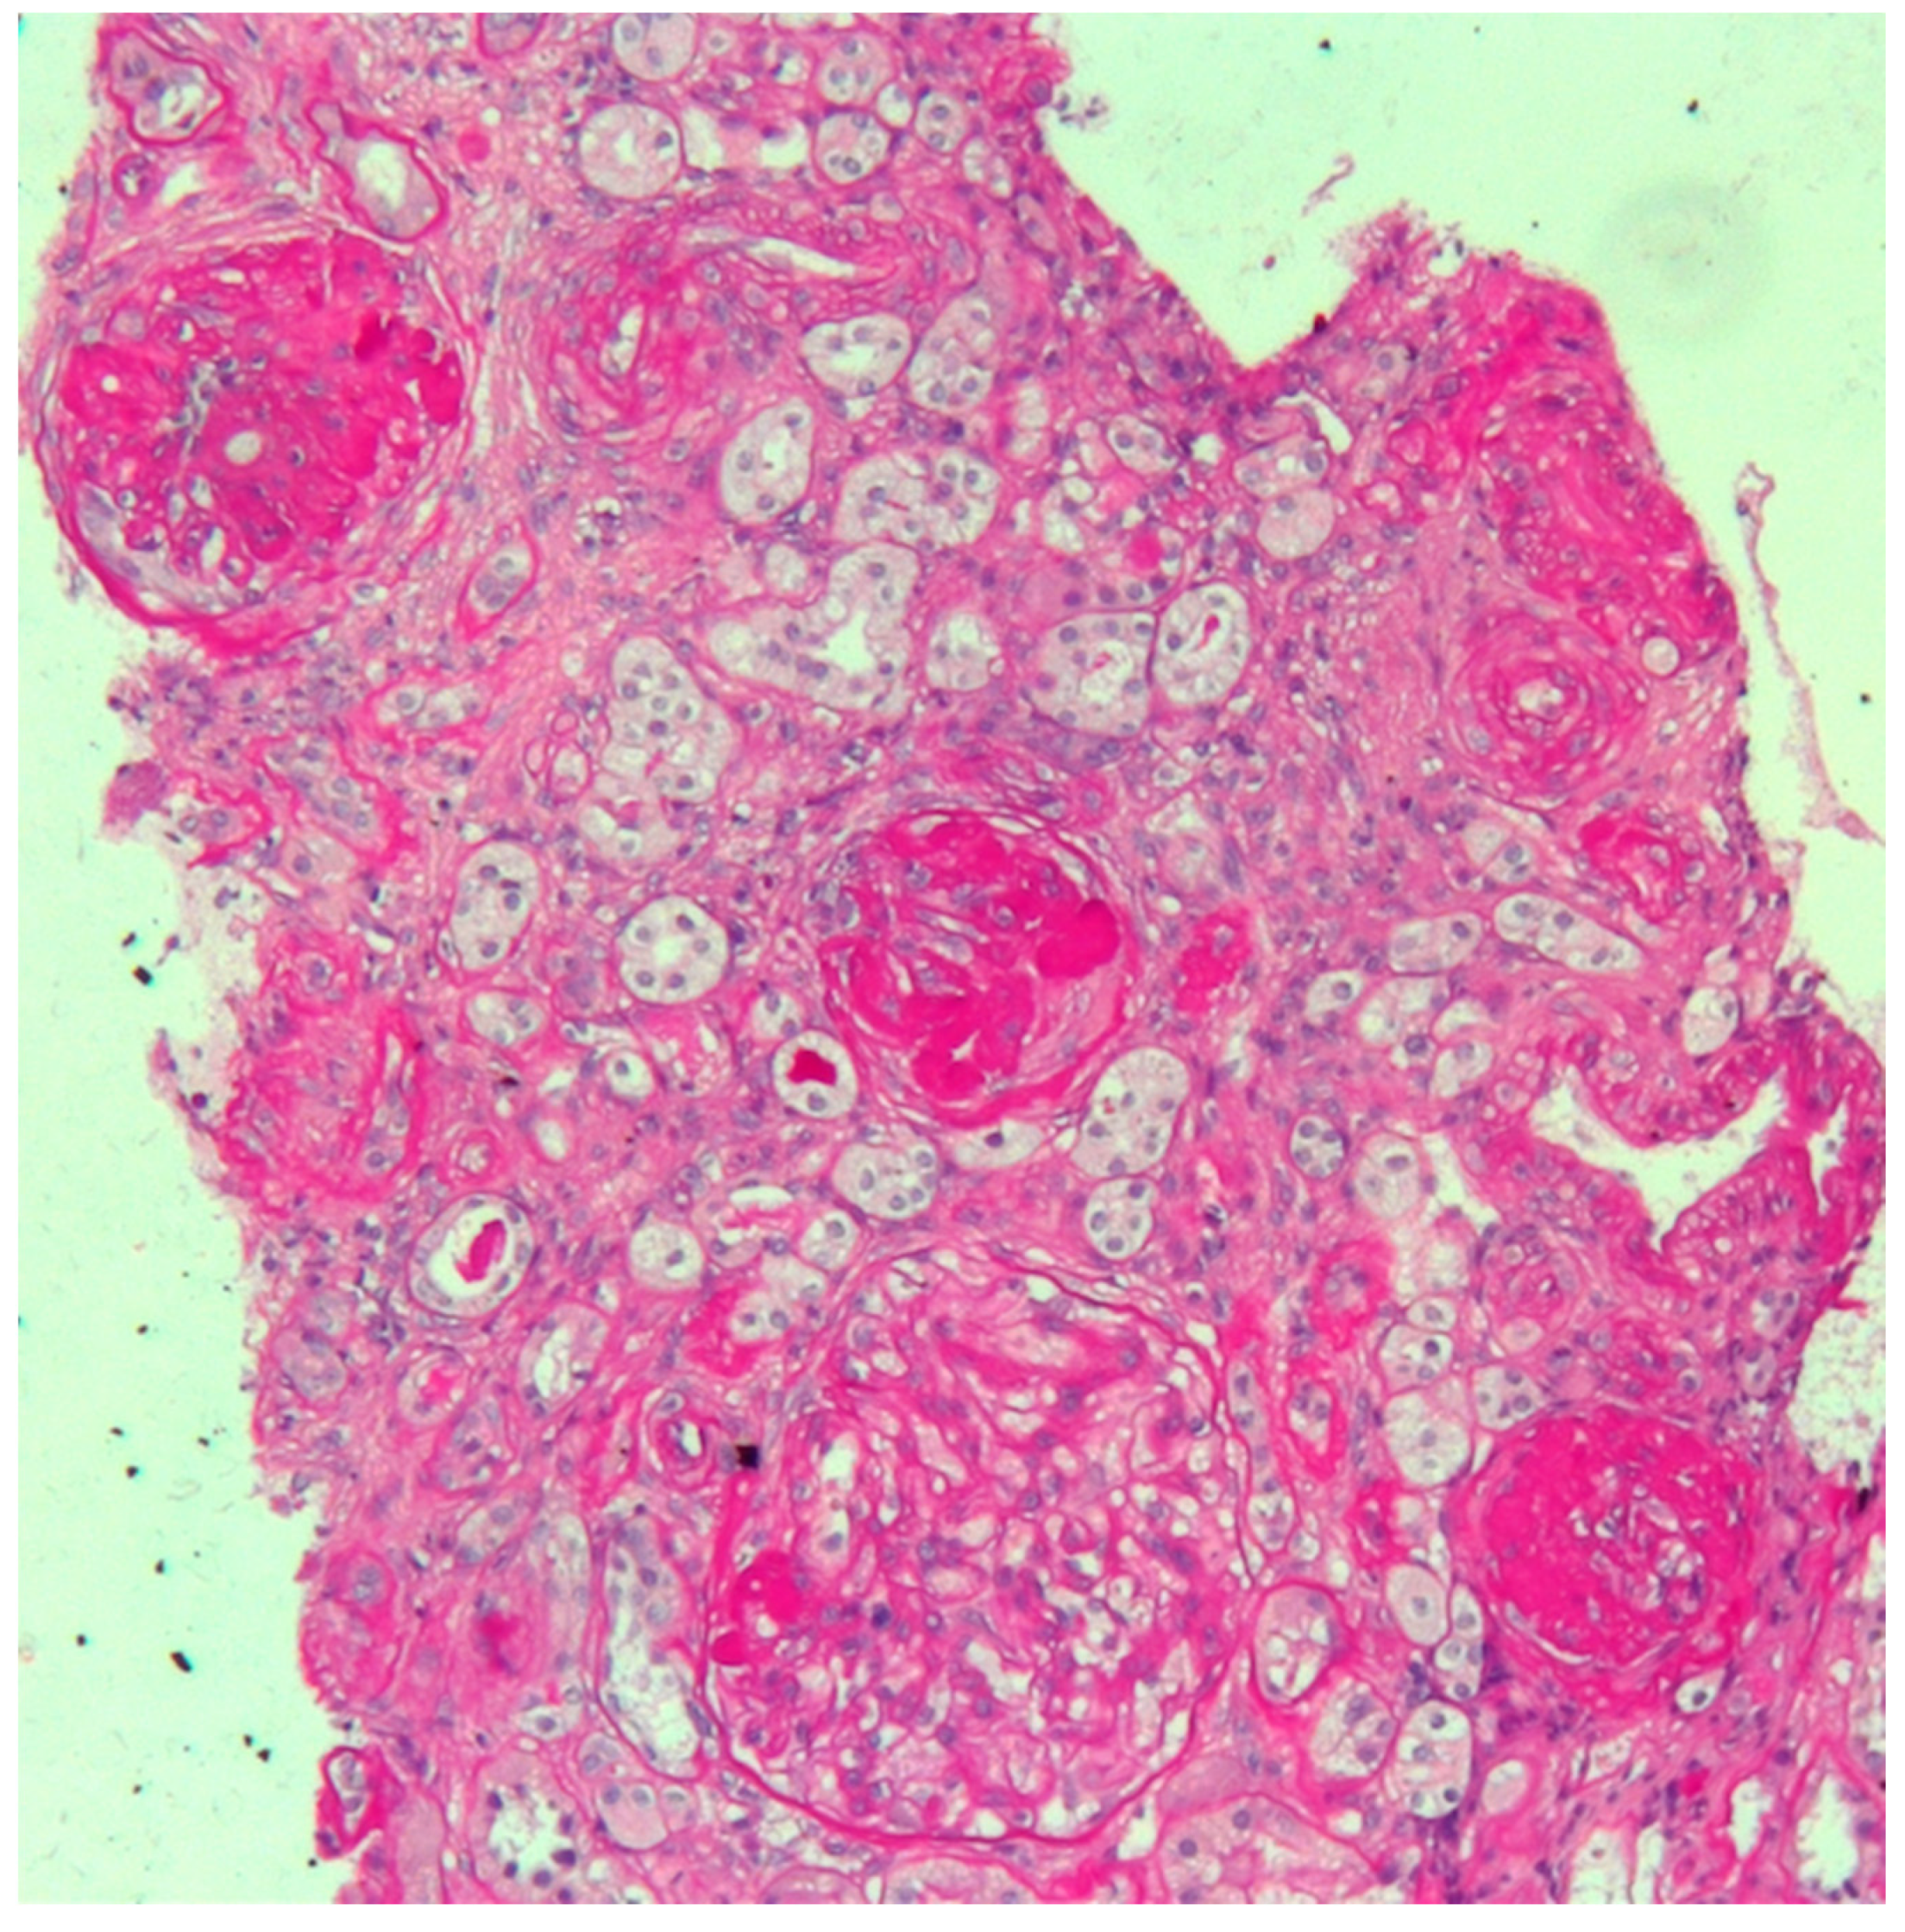

The woman’s medical history was characterized by early onset of non-insulin-dependent diabetes mellitus (at the age of 25), followed by Hashimoto’s thyroiditis at the age of 26. At the age of 30, one year prior to becoming pregnant, during a workup for infertility (ascribed to bilateral fallopian tube obstruction), she was found to have increased creatinine levels and proteinuria. A kidney biopsy was performed, and disclosed focal segmental glomerulosclerosis, with advanced sclerotic lesions (Figure 1). The patient’s mother was affected by Type-2 diabetes and mild CKD but the family history was otherwise uneventful.

The kidney biopsy in this case presents the features of glomerular sclerosis and of glomerulomegalia, thus suggesting a form of focal segmental glomerulosclerosis (FSGS), secondary to nephron loss and to hypertrophy of the remnant nephrons (Figure 1).

Figure 1. Kidney biopsy. Periodic Acid Schiff (PAS) staining, 20X: light microscopy showing three sclerotic glomeruli and a segment of sclerosis in a large hypertrophic glomerulus. Interstitial oedema with mild inflammatory infiltrate is also evident. Arterioles show marked thickening of tunica media.